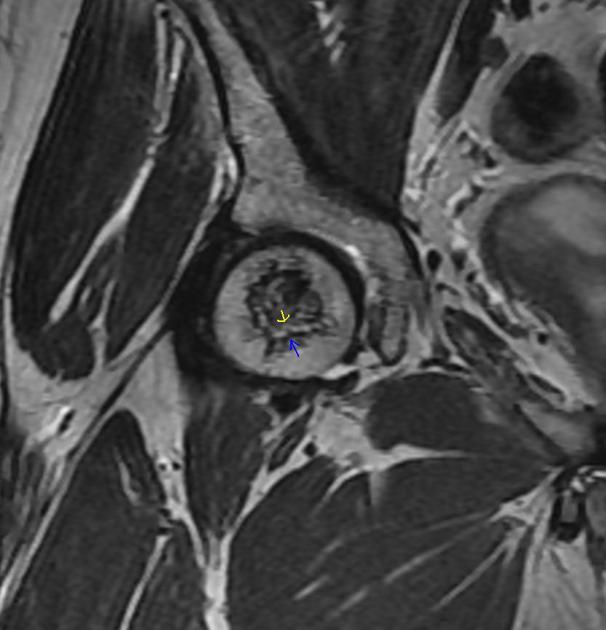

Diagnosis and sign?

AVN.

The “double line sign” is frequently seen on T2 weighted images in AVN (and bone infarcts) due to an inner bright line of granulation tissue next to an outer dark line of sclerotic bone.